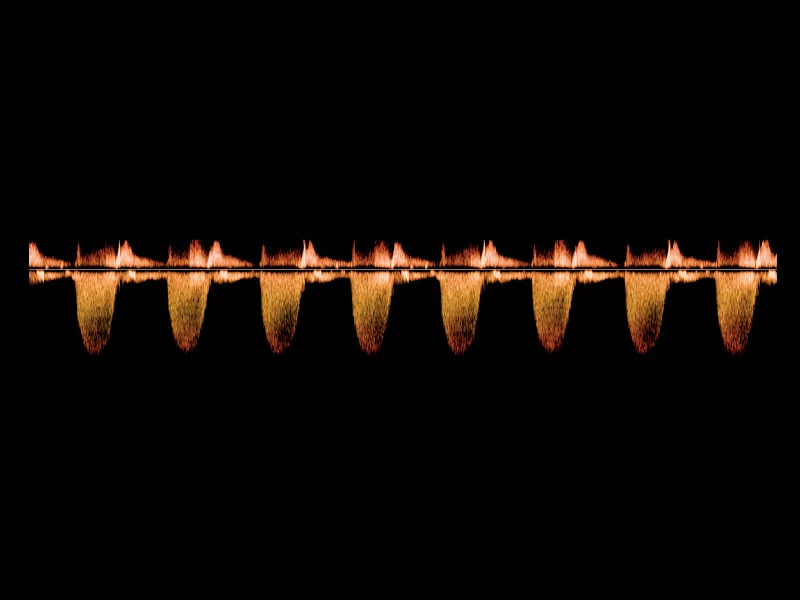

MyLab™9 Platform - Advanced CW Doppler processing chain for aortic stenosis quantification

MyLab™9 Platform - Advanced CW Doppler processing chain for aortic stenosis quantification

MyLab™C30 - Doppler - CW

MyLab™C30 - Doppler - CW